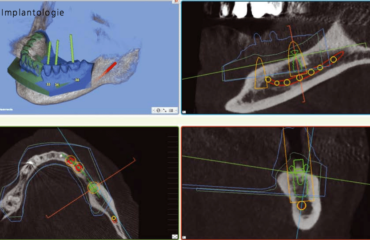

Au cours de ces dernières années, l’application clinique de la planification virtuelle d’opération guidée par gabarit est devenue un instrument d’insertion d’implants qui convient à la pratique. L’auteur de cet article exerce dans un cabinet privé en tant que spécialiste en chirurgie orale.

Il s’occupe du thème de l’«implantologie naviguée» depuis de nombreuses années et a été consulté lors du développement de plusieurs produits importants. Dans cet article, il souhaite exprimer son opinion sur les avantages qu’offre actuellement l’implantologie naviguée ainsi que sur les situations dans lesquelles il est préférable de choisir les méthodes conventionnelles.